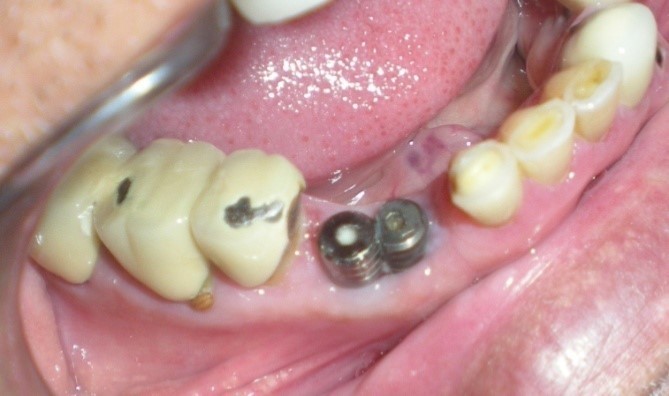

Unplanned implant placement or change in angulations of the implants due to anatomic limitations3,4 such as mandibular canal, mental foramen, nasal floor, sinus cavities or roots of the adjacent teeth, might result in close approximation of the implants (Figure 1), which poses tough challenges to the restorative dentist, who have to overcome certain technical difficulties for the fabrication of the prosthesis including making of a proper impression.

Figure 1.Radiograph – closely positioned implants.

Radiograph – closely positioned implants.

Healing abutments were cleaned and removed from mouth (Figure 2) and placed in a disinfecting solution. Direct impression coping (AlphaBio, Israel) was on one of the implants (SPI, AlphaBio, Israel) and secure it with long connecting screw (Figure 3).